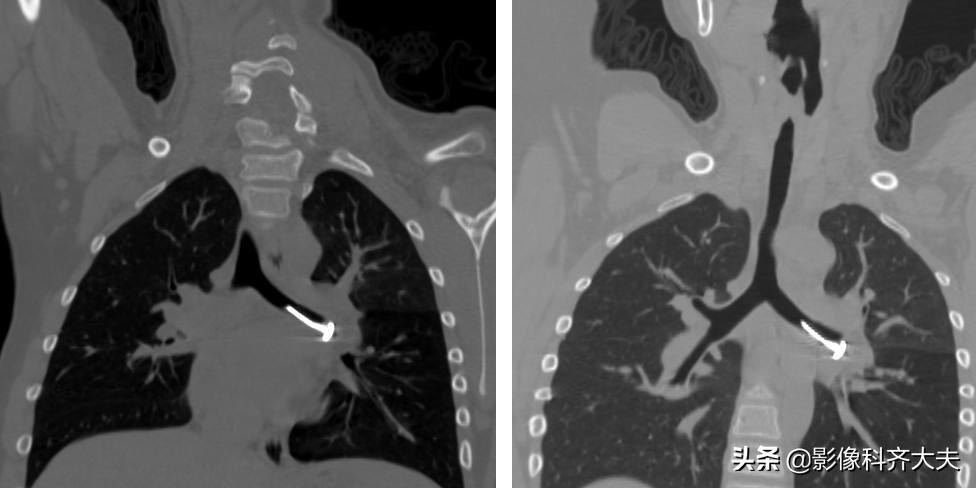

病例1、病史:患儿,女,一岁半,咳喘两周,病前有“开心果”吸入史。

图为轴位及冠状位重建图显示异物:红色箭头为异物的位置,冠状位显示尤为清晰。